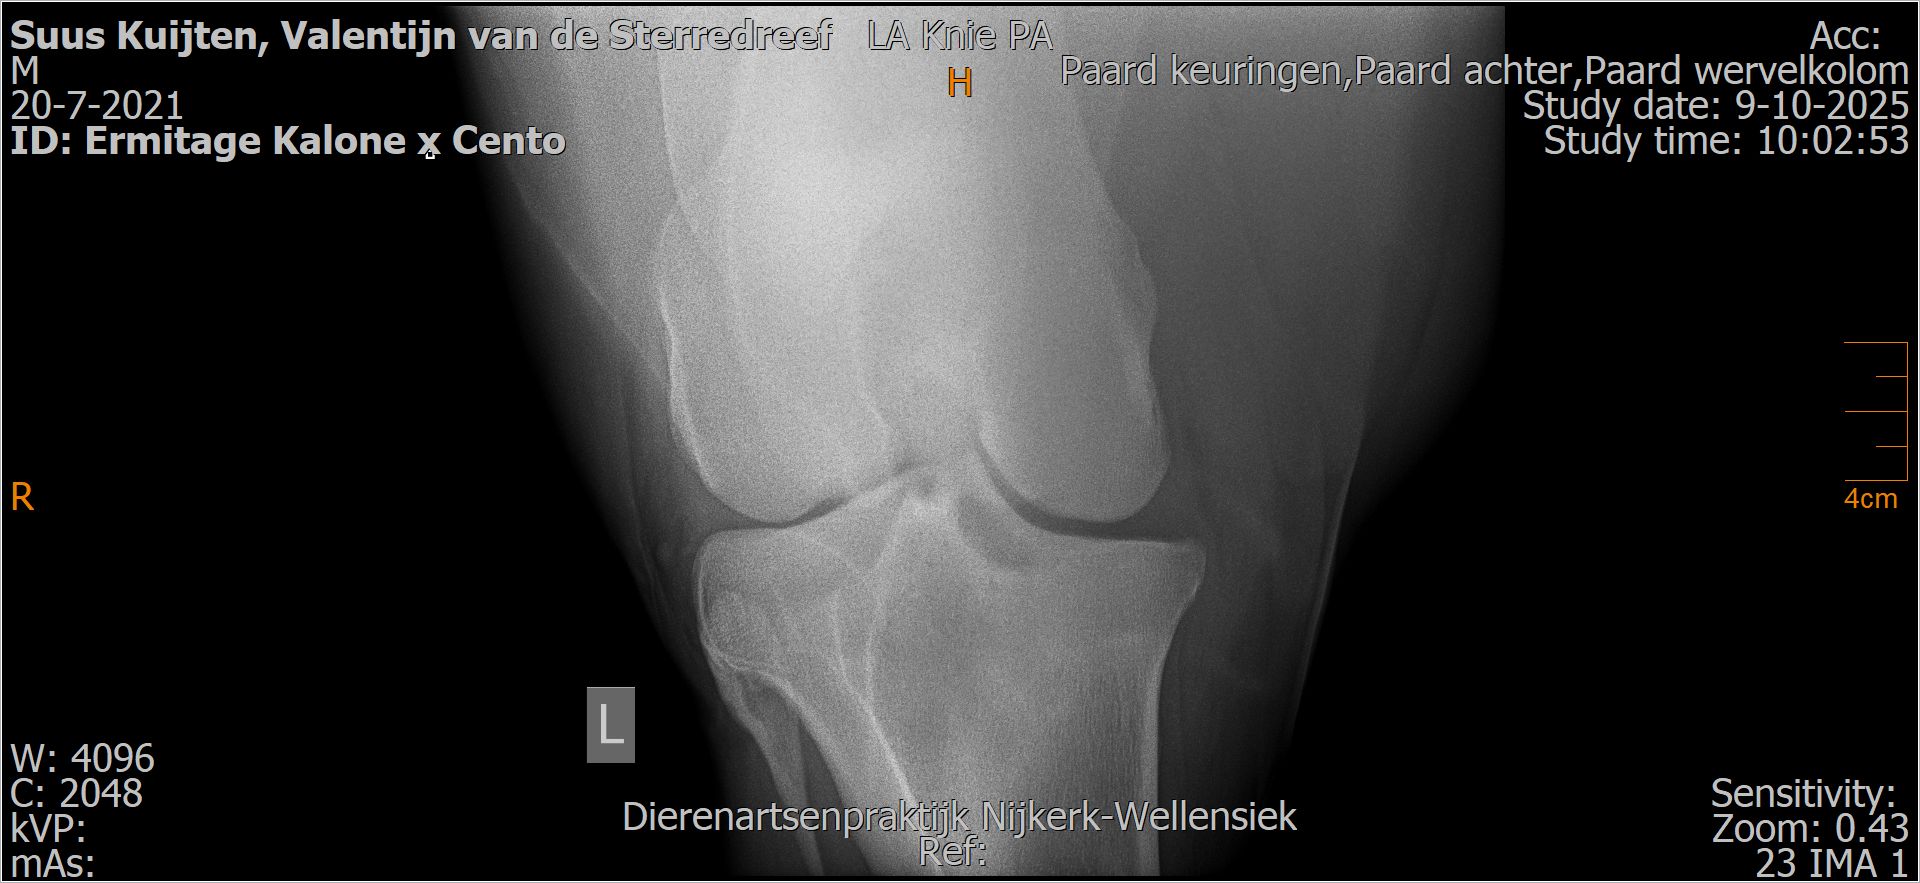

Valentijn van de Sterredreef

Röntgenfoto’s